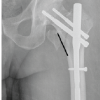

In our study, the mean age of the patients with IT fracture is 71.29 years with majority being in 71–80 years of age group (38.67%), followed by 32% in 61–70 years of age group. Among the 75 patients with IT fracture, 41 patients are males and 34 are females, amounting to 54.67% of males and 45.33% of females. In our study among 75 patients of IT fractures, 38 patients had right-side injury and 37 patients had left-side injury. Right side is common side in our study. In our study, we classified IT fractures according to Evan’s classification. Among 75 patients, 17 patients had Evan’s Type 1, Group 1 IT fracture; 21 patients had Evan’s Type 1, Group 2 IT fracture; 12 patients had Evan’s Type 1, Group 3 IT fracture; 18 patients had Evan’s Type 1, and Group 4 IT fracture and 7 patients had Evan’s type 2 IT fracture. In our study, mean operating time of PFN group is 92.80 min, MS-PFN group is 78 min and A2-PFN group is 66.8 min. Significant difference seen in PFN versus MS-PFN and PFN versus PFN-A2. There is no significant difference between MS-PFN and PFN-A2 group. In our study, mean blood loss in PFN group is 307.2 mL; in PFN-A2 group, it is 237.2 mL and in MS-PFN group, it is 246.4 mL. Significant difference is seen in PFN versus MS-PFN and PFN versus PFN-A2. There is no significant difference between MS-PFN and PFN-A2 group. In our study, mean radiological union in PFN group is 15.89 weeks; in MS-PFN group, it is 14.92 weeks; and in PFN-A2 group, it is 13.14 weeks. There is significant difference between PFN and PFN-A2 group in terms of union. In our study, we compared Harris hip score among three groups at post-operative 6 weeks, 12 weeks, 6 months, and 1 year. The results are tabulated in Tables 2 and 3, Graph 1. There is significant difference between PFN and PFN-A2 group in terms of functional outcome. In our study, we compared anterior thigh pain among three groups. Anterior thigh pain is more in PFN with 52%, followed by PFN-A2 with 40% and less in MS-PFN group with 27% (Table 4). PFN group had 12% shortening, 8% of screw cut out, 8% of SSI, 4% of varus collapse, and 4% of Z effect/reverse Z effect. PFN-A2 group had 4% shortening, no screw cut out, 8% of SSI, and 4% of varus collapse. MS-PFN group had 8% shortening, 4% of screw cut out, no SSI, no varus collapse, and 4% of Z effect/reverse Z effect (Table 5).

The average intraoperative blood loss in PFN group was 307.20 mL. PFN-A2 group had an average blood loss of 237.20 mL and MS-PFN had an average blood loss of 246.40 mL. Average blood loss was least in PFN-A2. In a study on PFN by Chopra et al. [10], average blood loss during surgery is 126 mL. In a study on MS-PFN by Jha and Ahmed [6], average blood loss is 130 mL and in a study on PFN-A2 by Rai et al. [11], average blood loss is 200 mL. In our study average radiological union in PFN group is 15.89 weeks; in MS-PFN group, it is 14.92 weeks and in PFN-A2 group, it is 13.14 weeks. Union in PFN-A2 is earlier compared to PFN and MS-PFN. In a study on PFN by Gadegone and Salphale [12], average time for fracture consolidation is 18 weeks. In a study on MS-PFN by Jha and Ahmed [6], average time for radiological union is 17.32 weeks and in a study on PFN-A2 by Rai et al. [11], it is 13.8 weeks. In our study, average mean Harris hip score for PFN-A2 is higher compared to PFN and MS-PFN at post-operative 6 weeks, 12 weeks, 6 months, and at 1 year. Harris hip score for PFN at 1 year is 82.26, for MS-PFN, it is 86.18, and for PFN-A2, it is 88.81. At post-operative 1 year, Harris hip score is higher in PFN-A2 group, followed by MS-PFN group compared to PFN group. All three implants have given good functional outcome according to Harris hip score. In a study on PFN by Mandice et al. [13], Harris hip score at 6-month post- operative is 88.75 and in a study on PFN-A2 by Rai et al. [11], it is 85.08 at 6-month post-operative. In our study, among 25 patients of PFN, 13 patients had persistent anterior thigh pain, among 25 patients of PFN-A2 of 240 mm, 15 patients had anterior thigh pain. However, in our MS-PFN group, it was significantly low, only 4 patients complained of anterior thigh pain out of 25 patients. In a study on PFN by Mukherjee et al. [14], 16 out of 53 patients had anterior thigh pain. In a study on PFN-A2 by Kumar et al. [15], 3 among 25 patients experienced anterior thigh pain. In our study, among 75 patients, 3 in PFN group, 2 in MS-PFN group, and 1 in PFN-A2 group had >1 cm of shortening. In a study on PFN by Chopra et al. [10], out of 125 patients, 3 had shortening. In a study on MS-PFN by Jha and Ahmed [6] out of 120 patients, 9 patients had shortening. Moreover, in a study on PFN-A2 by Rai et al. [11], among 25 patients, 2 patients had shortening. 2 patients in PFN group and 1 in MS-PFN group had complication of screw cutout; 2 in PFN group and 2 in PFN-A2 group had surgical site infection; 1 in PFN group and 1 in PFN-A2 group had varus collapse; and 1 in PFN group and 2 in MS-PFN group has Z effect/reverse Z effect. In a study on PFN by Chopra et al. [10], out of 125 patients, 5 had Z effect/reverse Z effect. In a study on MS-PFN by Jha and Ahmed [6] out of 120 patients, 14 patients had above-mentioned complications and in a study on PFN-A2 by Rai et al. [11], among 25 patients, 2 patients had varus collapse and 1 patient had surgical site infection.